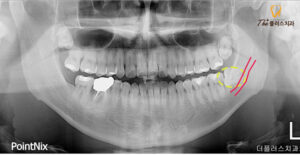

정밀한 진단을 위해

파노라마 사진을 촬영해 보았습니다.

사진을 보시게 되면 수평 매복 되어있는 모습을

보실 수 있는데 이 종류의 사랑니는

정상적인 치열에 대해 수평으로 위치하고 있어

다른 치아를 압박하고

치조골을 훼손할 수 있기 때문에

이러한 사랑니들은 보통 발치하는 것이 좋습니다.

조금 더 정밀한 진단과 안정적인 발치를 위해

CT를 촬영하여 사랑니의

정확한 맹출 방향과 치근의 휨 정도,

신경과 중첩된 모양 모두 정밀히 파악하여

발치를 진행하기로 하였습니다.